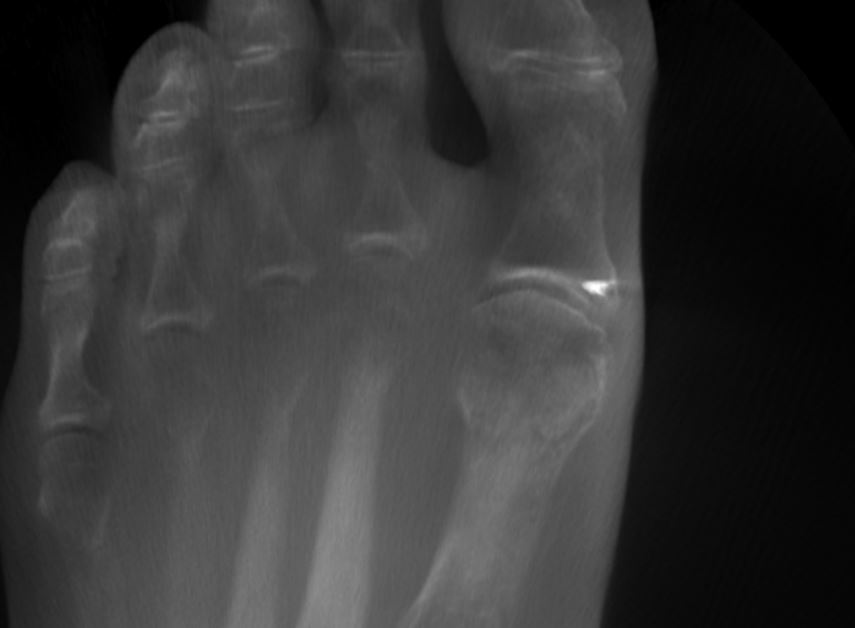

Turf Toe mit Ankerrefixation distal